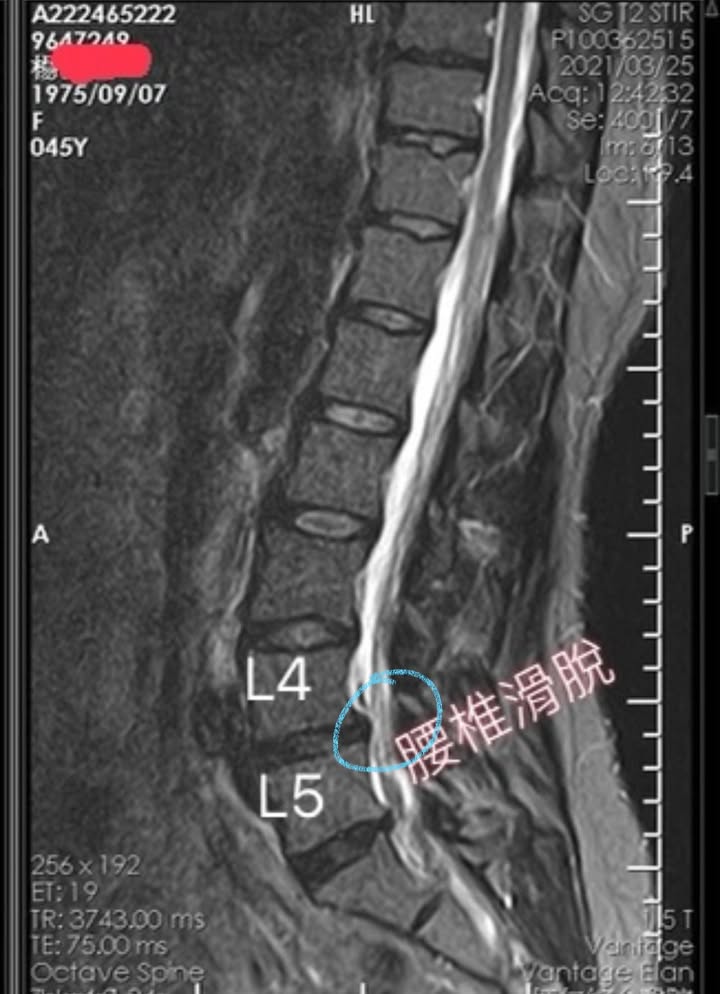

Cervical Spine Treatment Cases 腰椎治療案例 #巨大椎間盤突出醫案 #治療十二次提供前後MRI對比 #縱切面跟橫切面對比 #椎間盤突出為... 2021.09.03 ⭕️今天聽到患者說在某醫學中心開整段脊椎的刀 ,骨釘,骨水泥,人工椎間盤全上了,花... 2021.08.25 #典型下背手術失敗綜合症候群 #頸椎跟腰椎在短短幾年開了三次大刀 #腰椎融合固定支架... 2021.08.17 #馬尾神經症候群特殊醫案 #小便失禁合併下肢無力 #脊椎整合中醫微創逆轉勝 #脊刻救援... 2021.08.13 #骨刺髓核有可能吸收回去嗎?? #疼痛到無法行走的恐怖無法形容 #MRI核磁共振前後對比... 2021.08.14 #巨大椎間盤突出一定要開刀嗎? #兩家醫學中心外科醫師說很嚴重! #有沒有辦法逆轉勝... 2021.08.10 ❖ 椎間盤突出治療醫案 ❖晨起痛爆整個人無法工作心情沮喪 😂骨科醫師說復健如果沒效可... 2022.05.12 #天才年輕賽車手巨大椎間盤突出醫案 #八周治療完全逆轉勝康復 #重新回到合法賽車場競... 2021.07.20 #腰椎滑脫痛苦不堪 #右腳麻痛無法彎腰刷牙 #感謝桃園市楊小姐熱情見證 #患者親自贈送... 2021.06.15 #巨大椎間盤突出醫案 #真的逆轉勝超感動 #三個月治療完全徹底改善 #脊刻救援成功 #徹... 2021.06.12 ⭕️L4L5巨大椎間盤突出治療醫案 🌟八週之內解除危機逆轉成功 😁順利降級成功解封印 💪... 2021.07.08 #腰椎多節椎管狹窄治療醫案 #腎臟病患者可接受中醫微創筋膜療嗎? #感謝台北市信義區張... 2021.06.01 #腰椎手術失敗綜合症候群 #感謝桃園呂伯伯熱情見證 #何時必須優先考慮再次動刀 #脊刻... 2021.07.31 #感謝新店吳先生熱情見證 #車禍後導致椎間盤突出醫案 #傳統復健六周無效痛苦不堪 #脊... 2021.05.29 #椎間盤突出治療醫案 #破紀錄三週解決 #真的逆轉勝 #感謝新莊周先生熱情見證 #脊椎整... 2021.05.26 ← 上一頁 6 7 8 9 10 下一頁 →